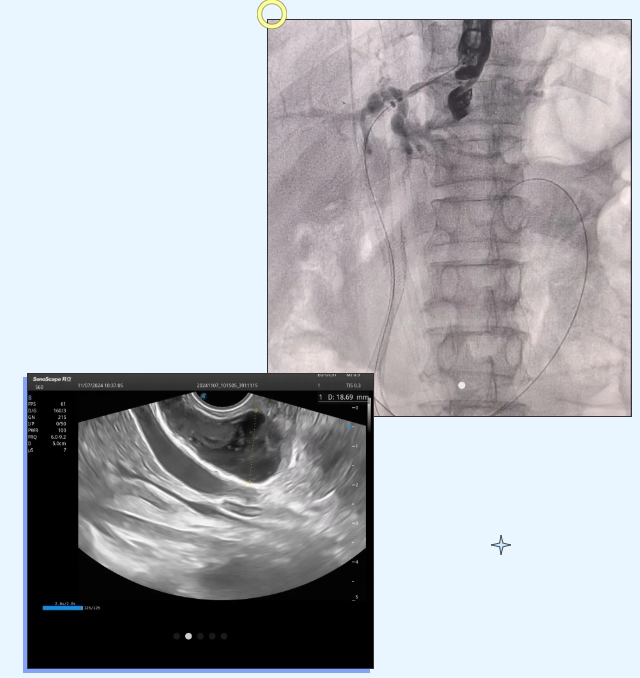

近日,石家庄市第五医院成功开展一例超声内镜引导下经胃穿刺胆管支架置入术+胆管胃吻合术,帮助一名胰头癌患者解除胆管梗阻的痛苦。

患者为老年男性,诊断胰头癌,因出现皮肤及眼睛发黄来到石家庄市第五医院感染二科(传染性疾病和肝病合并免疫系统疾病科)就诊。经检查,患者总胆红素高出正常人的几十倍,医生分析,这是因为患者胰头部肿瘤压迫胆总管造成的梗阻性黄疸。为制定切实有效的治疗方案,感染二科主任申请了院内多学科会诊。由感染二科牵头,组织消化内镜室、介入医学科、外科、功能科、放射科等专业科室的专家共同制定治疗方案,经过充分讨论最终形成一致意见:患者因肿瘤侵犯十二指肠,无法行ERCP术,为不影响术后患者的生活质量,决定由消化内镜室为患者进行超声内镜引导下经胃穿刺胆管支架置入术+胆管胃吻合术。

为尽快解决患者的痛苦,消化内镜室很快为患者安排了手术。手术操作中,医生在超声内镜引导下,将穿刺针经胃穿刺到肝内胆管,后进入胆总管穿过十二指肠乳头,进入十二指肠。放置导丝后,沿导丝于胆总管放置一枚支架,再顺着导丝在肝内胆管与胃之间放入一枚支架,这就好比为胆道梗阻的患者打通了一条“通路”,即胆总管支架,并且架一座“桥”,即肝内胆管与胃支架,从而使胆汁通过支架既能顺着生理通道(胆总管)引流至十二指肠,也能通过肝和胃之间的通道引流至胃腔,避免后期肿瘤再次增长压迫造成二次梗阻。经过1小时30分钟的紧张手术,患者生命体征平稳,手术顺利完成。术后第二天,患者恢复良好,复查患者肝功能,总胆红素和黄疸下降,恢复了饮食并下床活动,手术治疗效果明显。